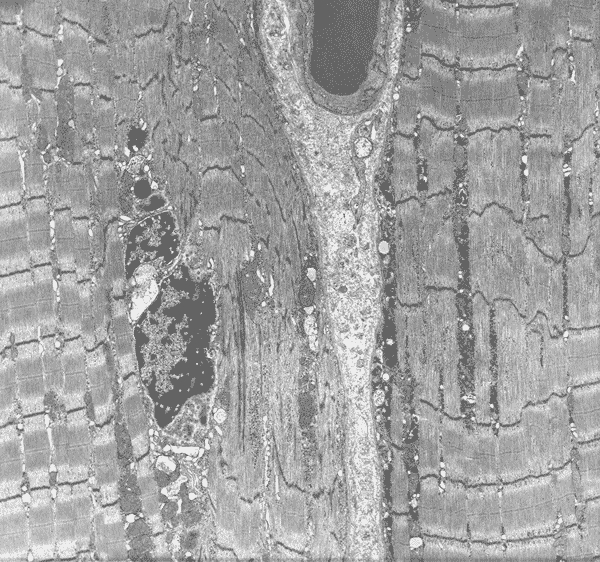

The myofibrils of the core (in between àÝ) are not in the same register with the surrounding myofibrils. The I-bands are reduced in length and the Z-disc is fussy.